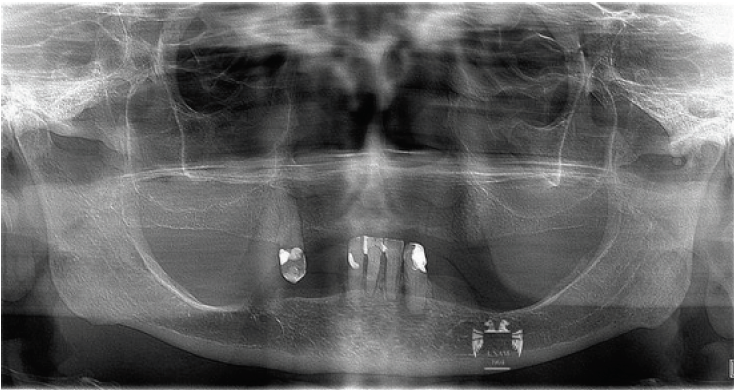

La prueba de metal se verificó de forma intraoral, mediante radiografías y la técnica de Sheffield para confirmar la pasividad (Figura 3), y se ajustó la oclusión. Después de confirmar el ajuste de las prótesis, se hizo la prueba de porcelana24, se verificó el esquema oclusal en función de grupo bilateral con cúspides de aproximadamente 22° y se dejó sin guía anterior para evitar la delaminación de los dientes anteriores25. Las prótesis finales se sometieron a la prueba de porcelana y se mandaron glasear al laboratorio y después se atornillaron en boca con un torque de 15 Newtons.